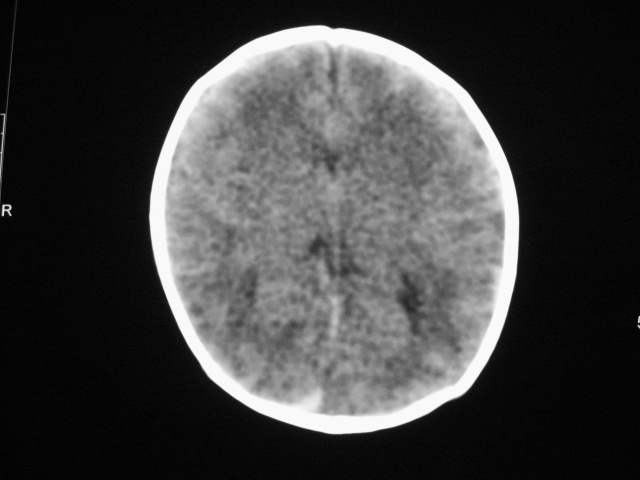

早产儿,1天,饮食呕吐,

双侧额叶见片状低密度灶,皮髓质分界模糊.患儿前囟略饱满,

患儿头颅ct示:皮质薄,髓质密度减低,脑回宽,脑沟浅,脑室系统无殊,中线结构居中,符合:早产儿颅脑ct改变。